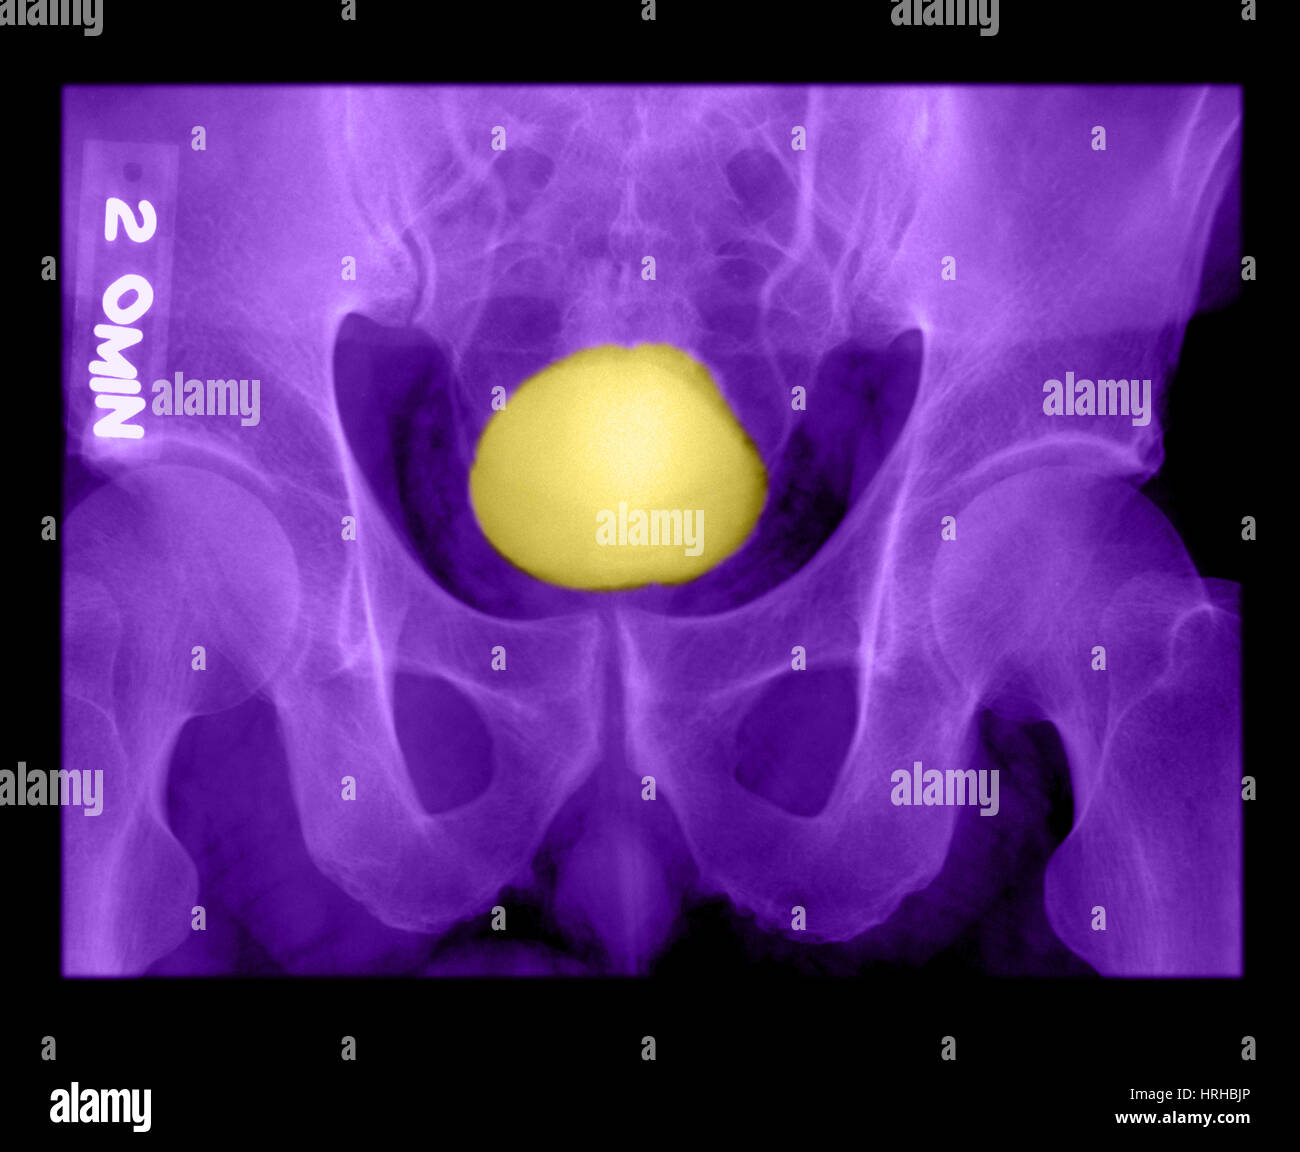

Case number: 2. X-ray of urinary bladder, taken on 03 O | Open-i

I.V.P is an X-ray Exam of Urinary Tract after Injection Contrast Media …

Comparison Of Intravenous Pyelogram Or Ivp Is An Xray Exam Of Urinary …

Film IVP, 30 minutes after injection of contrast media, of a lymphoma …